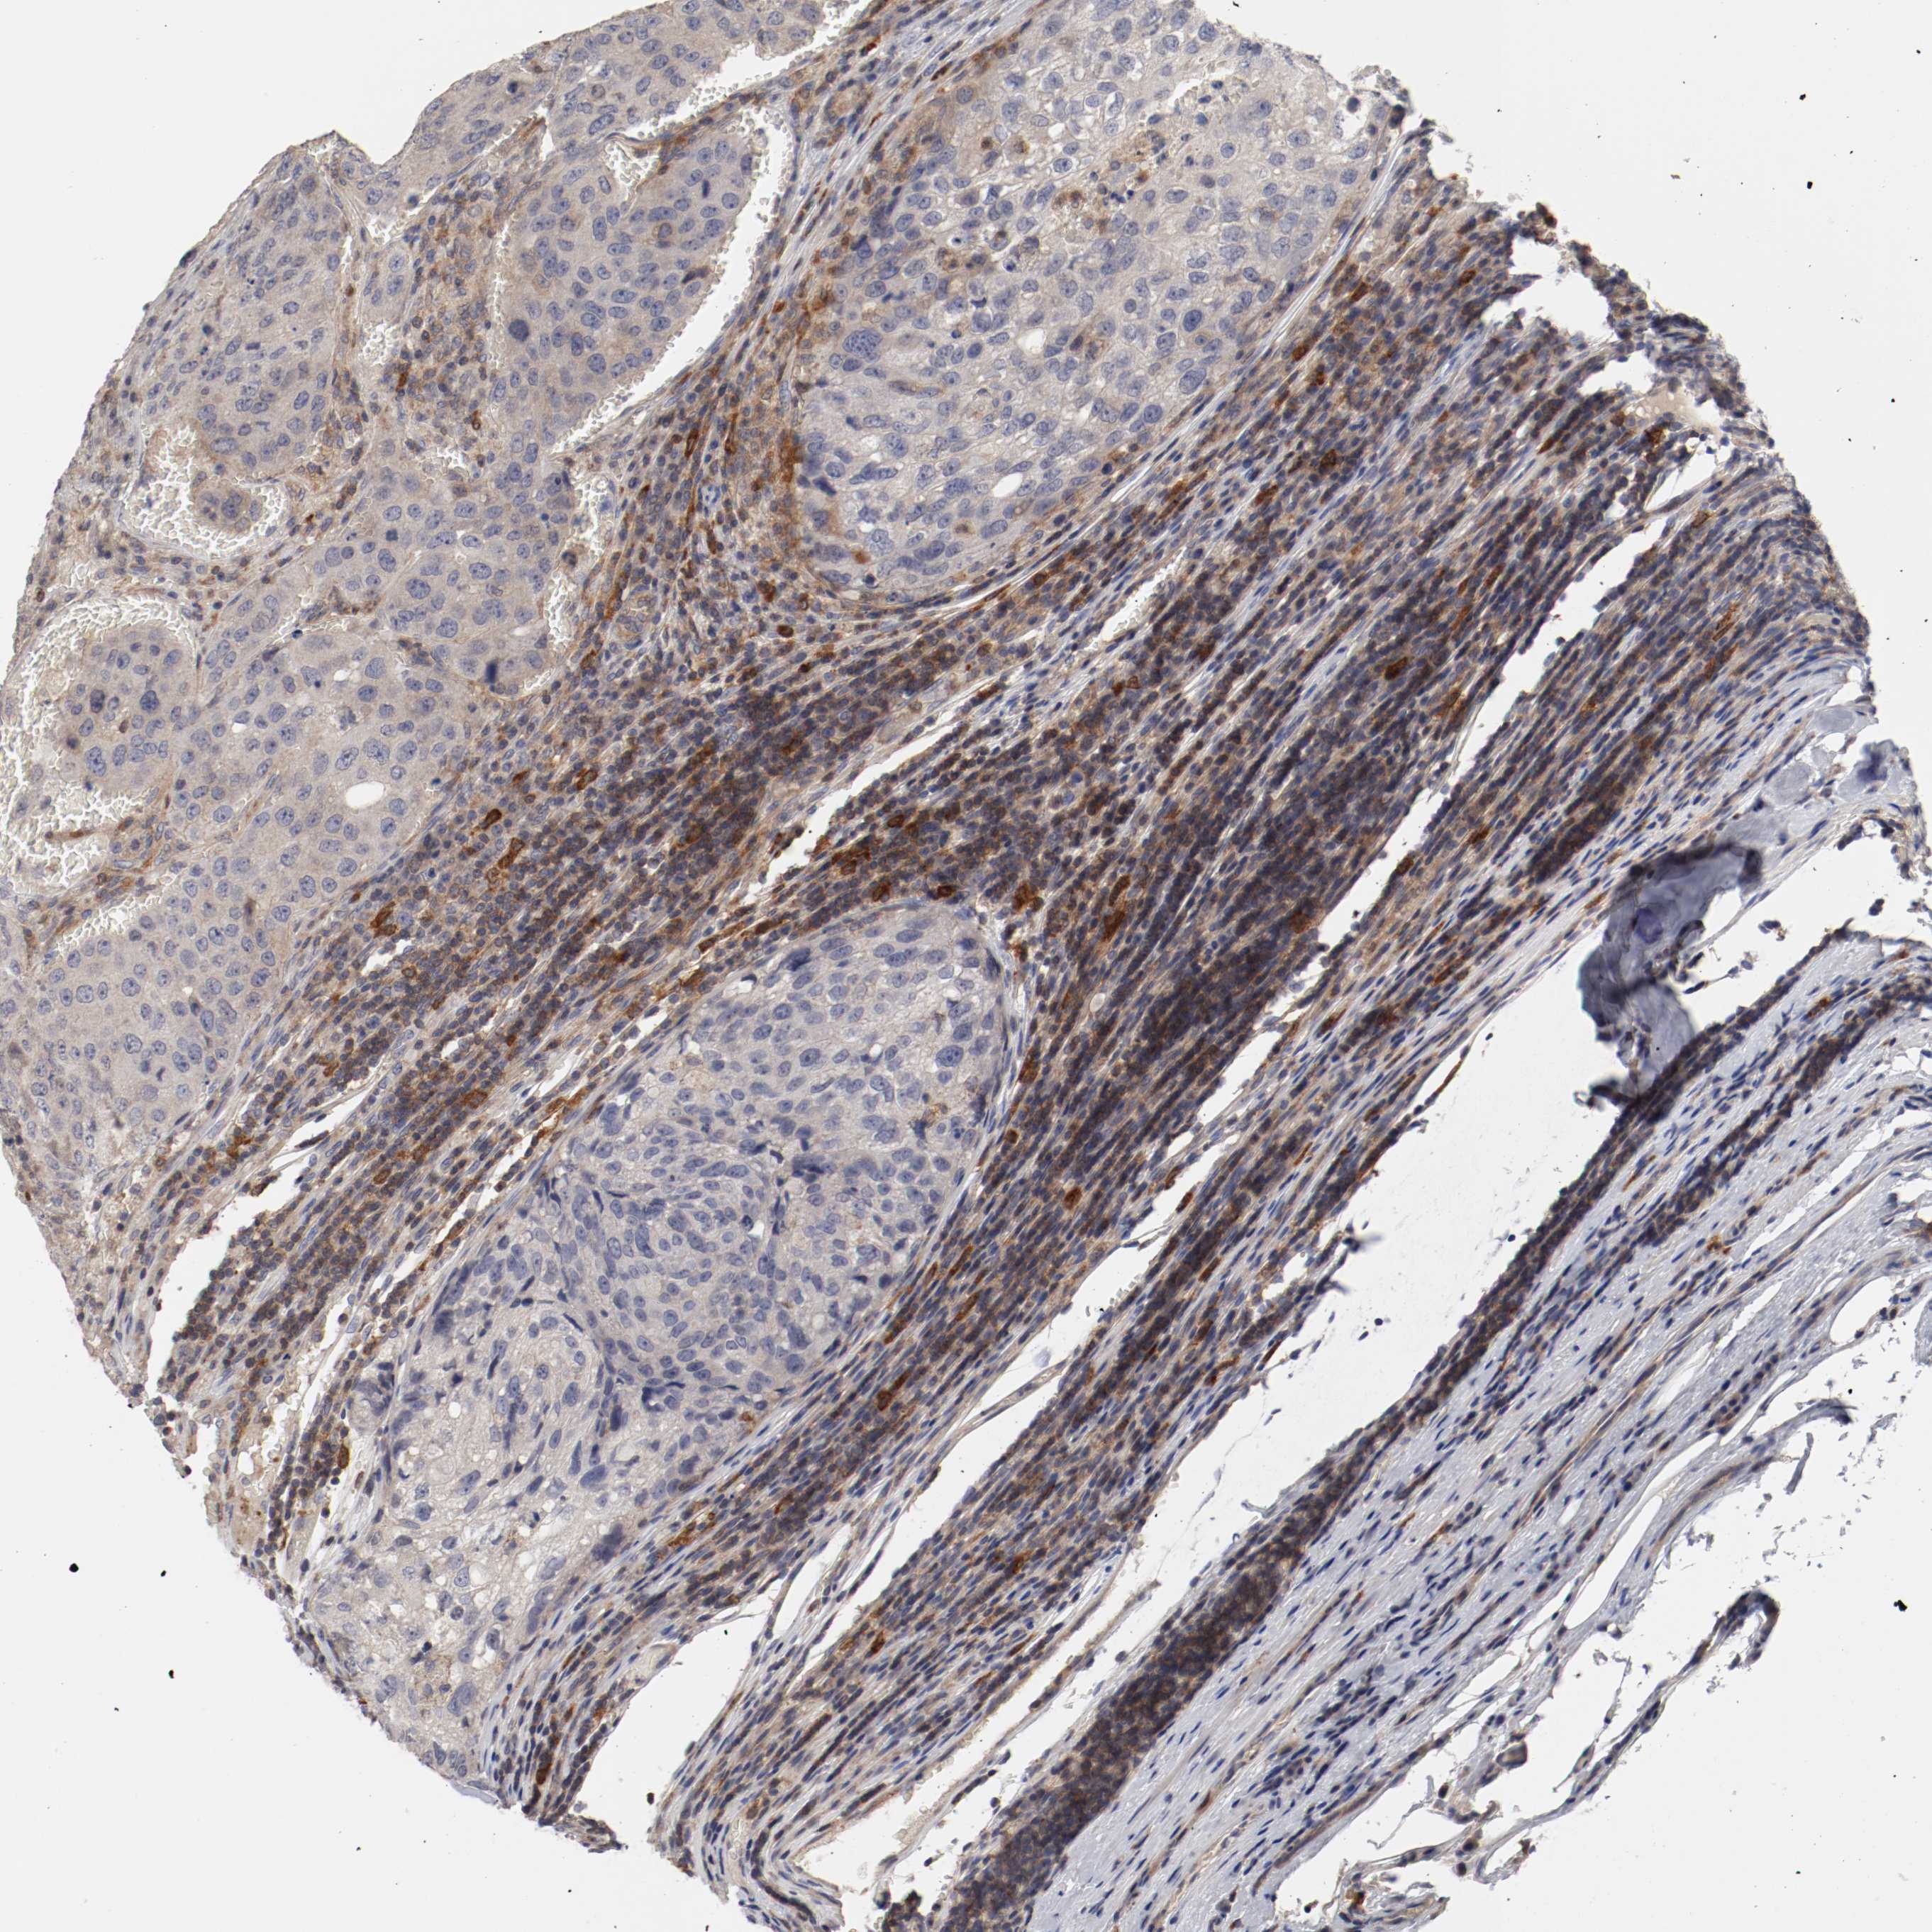

UROTHELIAL CANCER - Protein expressioni

A mouse-over function shows sample information and annotation data. Click on an image to view it in a full screen mode. Samples can be filtered based on level of antibody staining by selecting one or several of the following categories: high, medium, low and not detected. The assay and annotation is described here.

Note that samples used for immunohistochemistry by the Human Protein Atlas do not correspond to samples in the TCGA dataset.

Antibody stainingi

Antibody staining in the annotated cell types in the current human tissue is reported as not detected, low, medium, or high, based on conventional immunohistochemistry profiling in selected tissues. This score is based on the combination of the staining intensity and fraction of stained cells.

Each image is clickable and will lead to virtual microscopy that enables deeper exploration of all samples and also displays staining intensity scores, fraction scores and subcellular localization as well as patient and tissue information for each sample.

Antibody HPA027956

Antibody CAB004350

Urothelial carcinoma, Low grade

Urothelial carcinoma, High grade